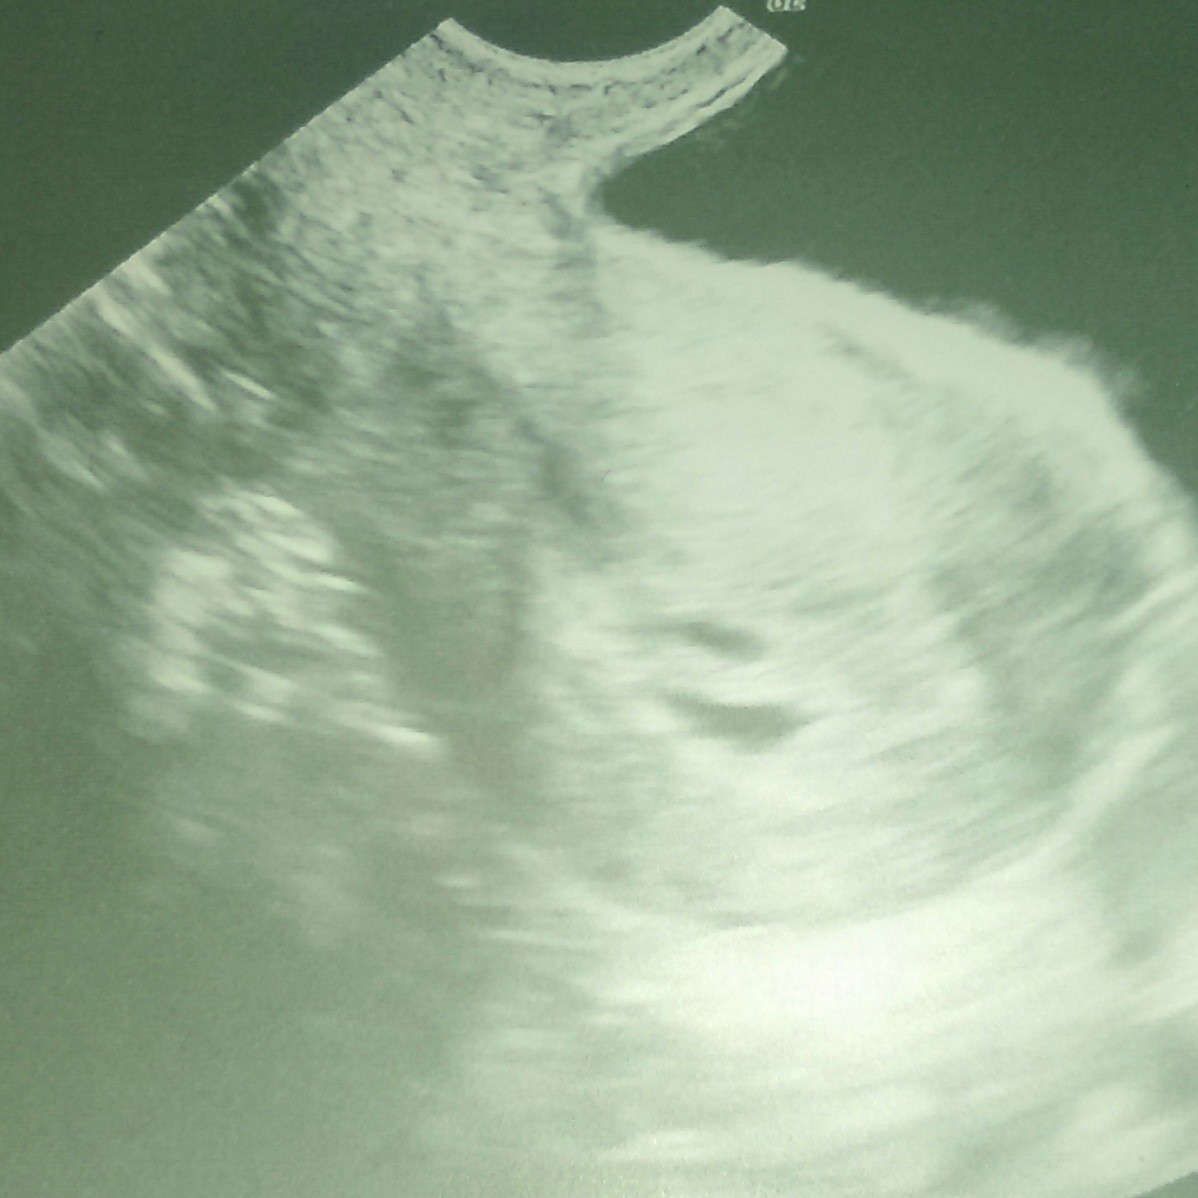

Po tym nocnym krwawieniu pojechałam do lekarza. Moja pani doktor niestety na urlopie, ale przyjął mnie inny. Zmienił leki, trochę się martwię, bo nie znam w ogóle tego lekarza... ale co najważniejsze... mam zdjęcie dwóch Maluszków

tylko jeden jest bardzo słaby i lekarz powiedział, że ciężko mu będzie nadgonić.... cieszę się i smucę jednocześnie. jak zwykle![]()